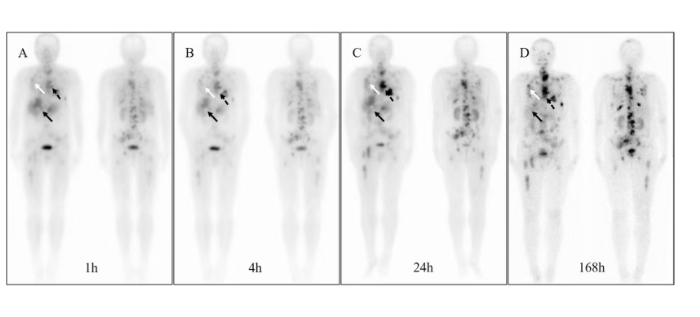

该成果凸显了PET显像技术在神经疾病早期发现与机制研究中的价值。Aβ PET可直观显示脑内淀粉样蛋白沉积情况,而Tau PET能精准定位神经原纤维缠结分布,两种技术的结合为评估疾病进程提供了多维视角。研究表明,对伴有骨关节炎的阿尔茨海默病高危人群,早期进行PET筛查与炎症控制,可能为干预赢得关键时间窗。